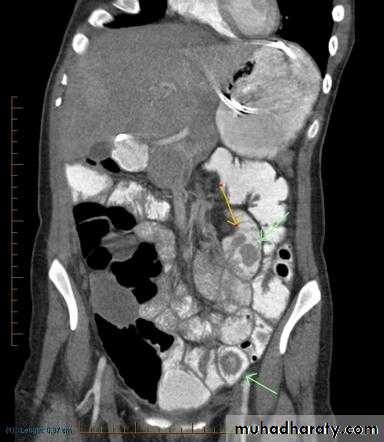

Intussusceptions'

Intussusceptions' occurs when one segment of bowel is pulled into itself (or a neighboring loop of bowel) by peristalsis.It is an important cause of an acute abdomen in children and merits timely ultrasound examination and reduction to preclude significant sequelae including bowel necrosis.

Intussusception may also occur in the adult population where it is usually caused by a focal lesion acting as a lead point.

Abdominal plain film

Abdominal x-rays may demonstrate an elongated soft tissue mass (typically in the right upper quadrant in children) with a bowel obstruction proximal to it.